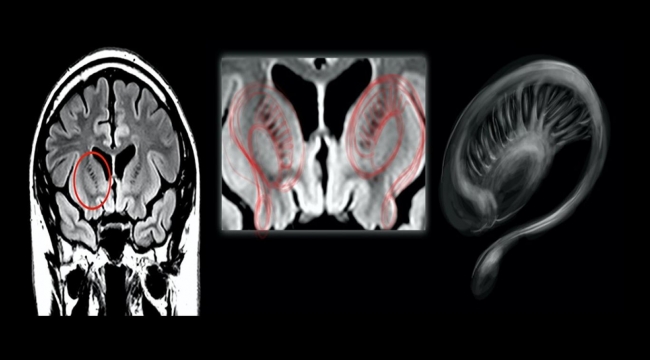

Muhabir Thobey Champion'ın isteği üzerine bu kişilerin MR görüntülerini tarif eden profesör, "Multipl skleroz hastası birinin MR'ına baktıysanız, beyaz cevher hastalığı denen bir şey görürsünüz. Yara izi vardır." ifadelerini kullandı:

"MR boyunca dağılmış büyük beyaz bir leke veya birden fazla beyaz leke görürsünüz. Bu aslında bağışıklık sisteminin beyne saldırdığı ölü dokudur. Pilotların beyin görüntülerine en yakın durum buydu. Bir şeylerin yanlış olduğunu hızla görebilirsiniz."